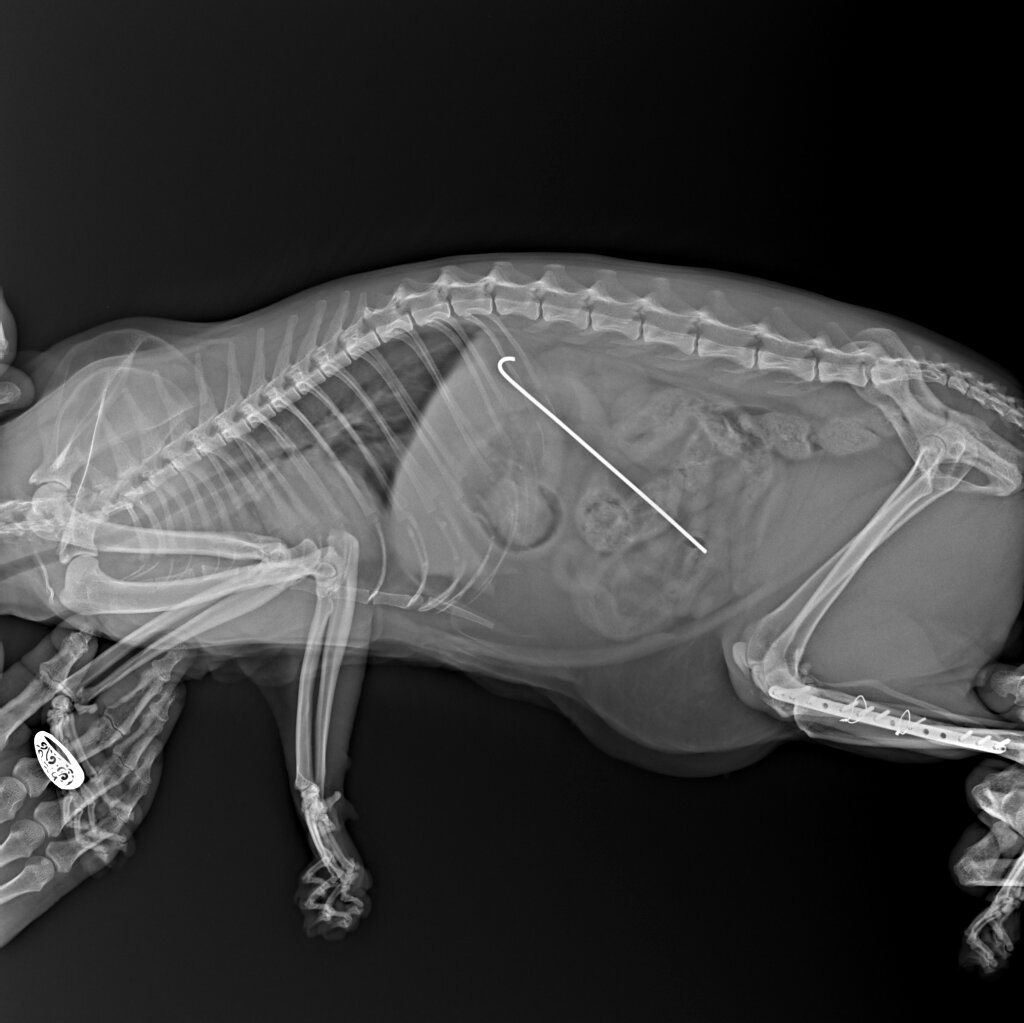

На рентгеновском снимке, который я приложил ниже, вы наверняка заметили инородное тело, расположенное в мягких тканях в области ребер.

Ранее специалистами другой ветеринарной клиники проводилось хирургическое вмешательство на задней лапе, направленное на сращивание перелома.

Операция прошла прошла успешно, питомец был активен, двигался, а затем его самочувствие ухудшилось.

Некоторое время животное было вялым, апатичным, но далее все вошло в норму.

Владельцы решили не оставлять данную ситуацию без внимания и обратились к нам.

Мы сделали снимок и увидели, что спица, которая была вставлена в заднюю лапу мигрировала аж в область ребер.

Миграция спиц встречается довольно часто, но чтобы так далеко...

Такое я увидел впервые за все годы своей практики!

Удивительно также то, что спица не нанесла абсолютно никакого вреда здоровью животного.

Она абсолютно без последствий для кота проследовала столь долгий путь по организму, лишь слегка доставив ему беспокойство.

Конечно же, мы ее извлекли, но этот случай однозначно останется у меня в памяти на долго.